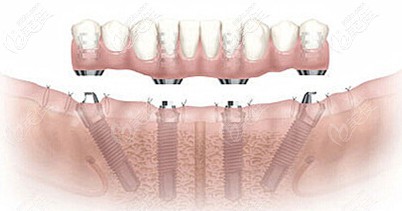

曾带领着种植团队把复杂软硬组织增量、All-On-Four半/全口种植牙、Comfour系统的即刻种植以及穿颧穿翼V-Ⅱ-V等种植技术应用于临床。